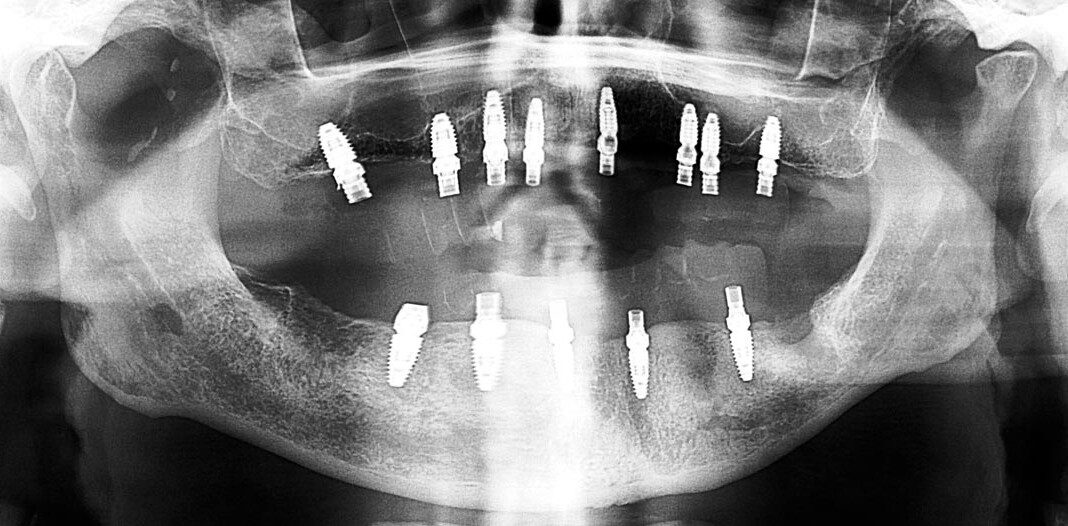

Pre-op, Panoramic x-ray. Note: Excellent bone in the upper front, reasonably good bone everywhere else.

Lower teeth extracted, some bone removal lower, 8 upper implants, 5 lower implants, lower immediate temporary bridge.